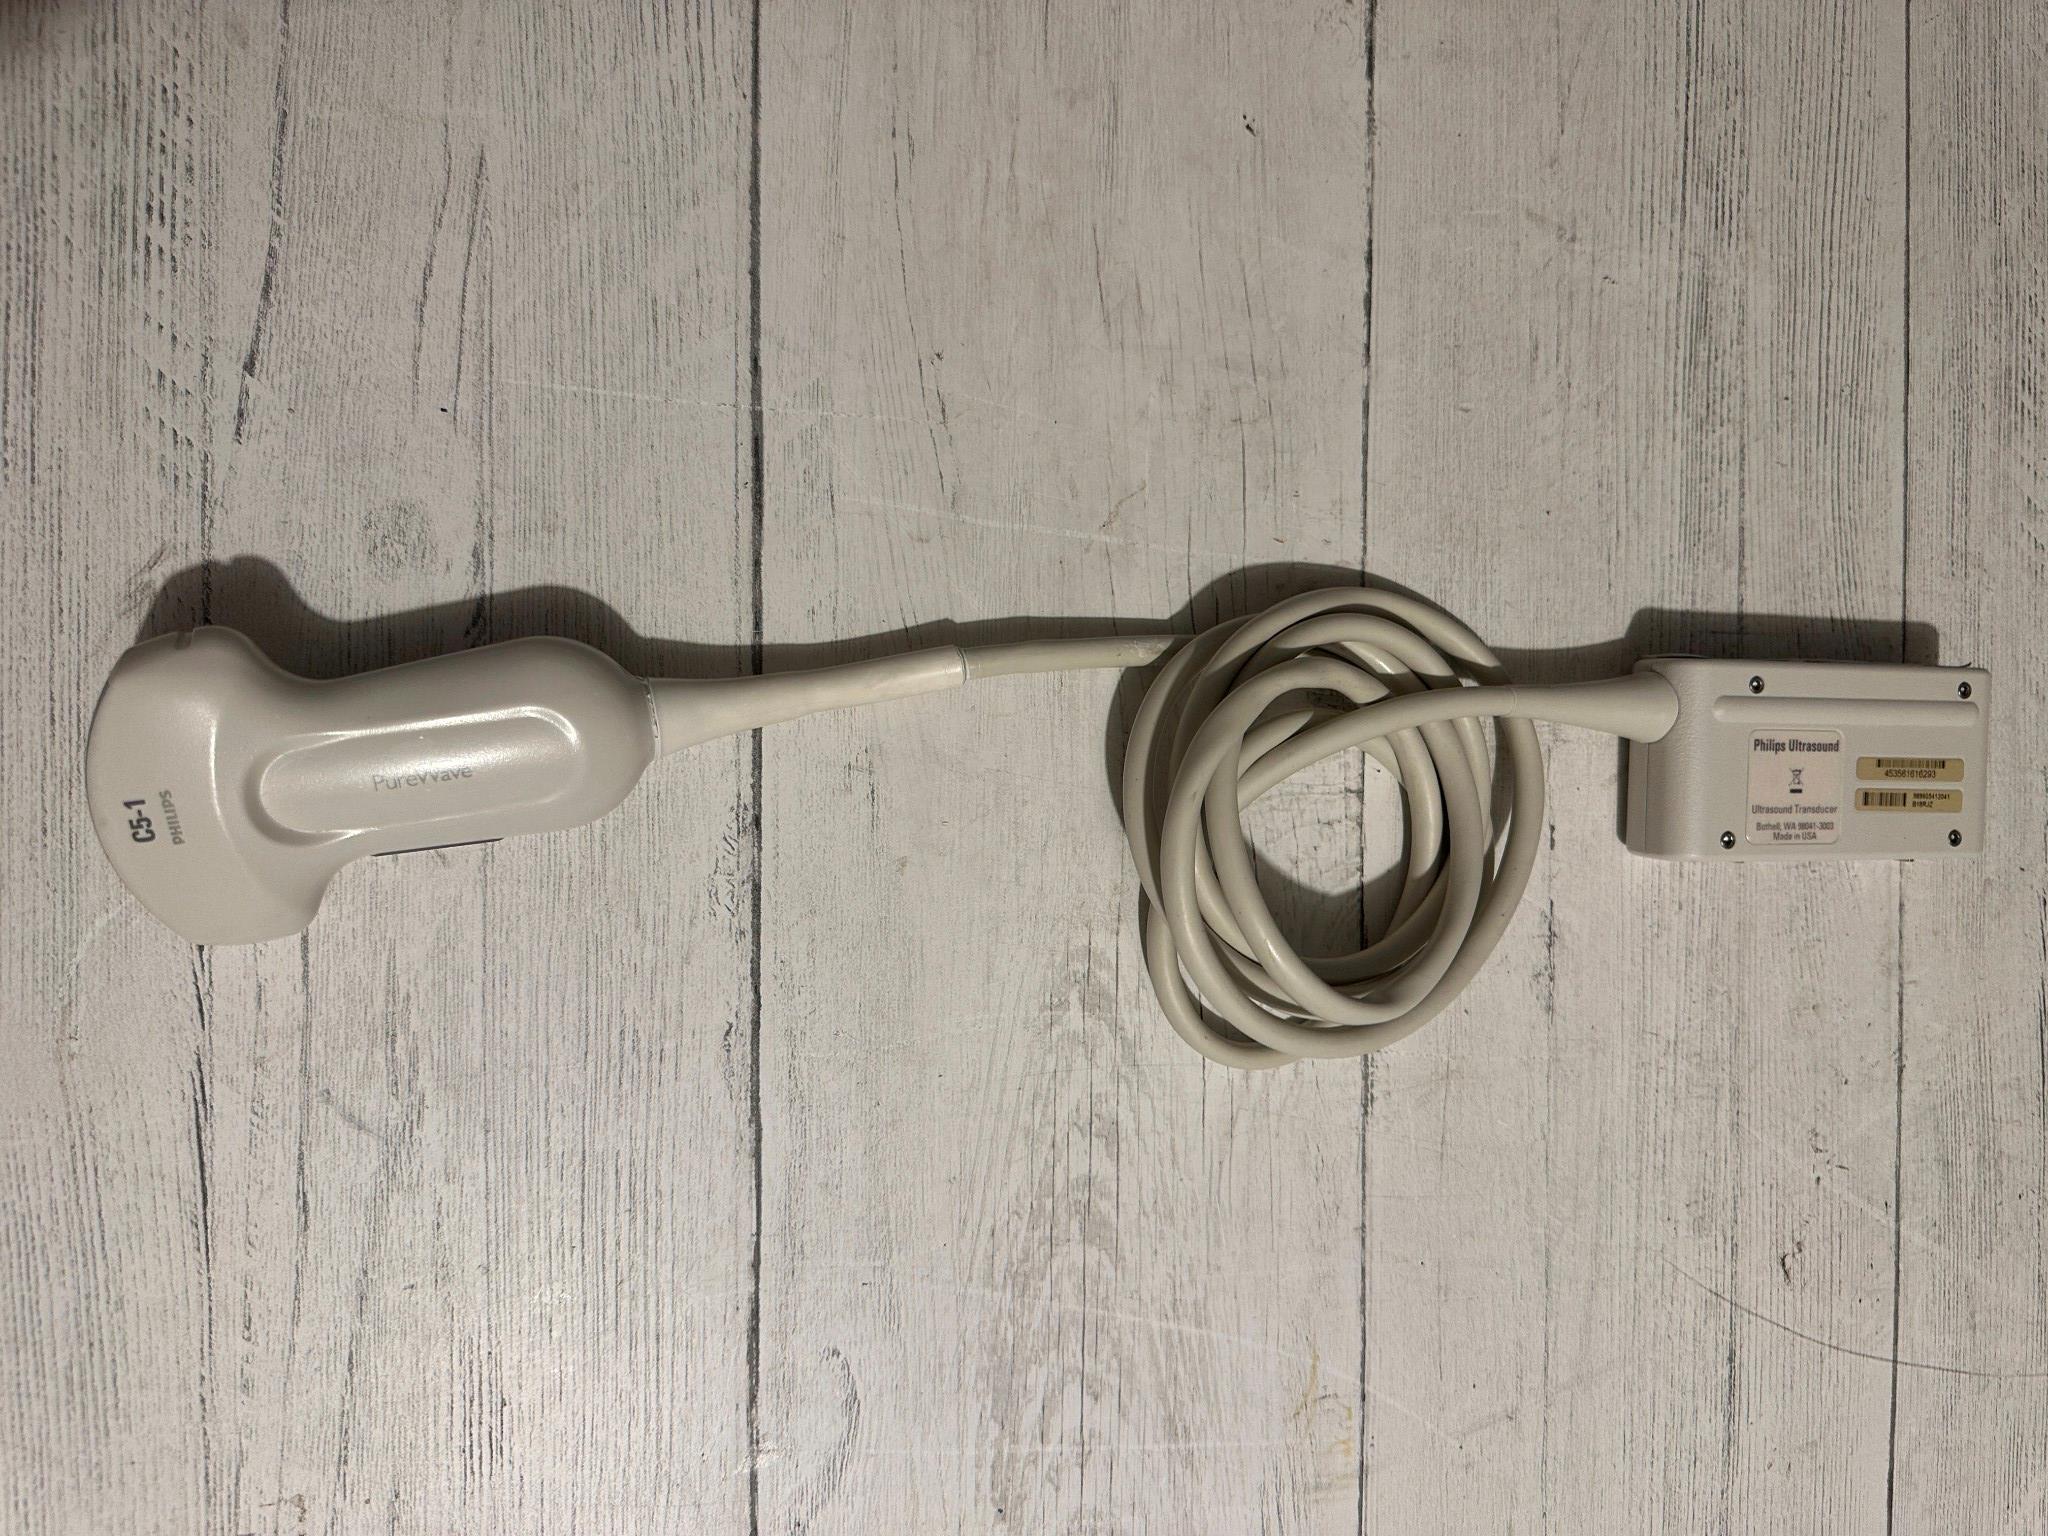

DIAGNOSTIC ULTRASOUND MACHINES FOR SALE

GE RSP6-16-RS Ultrasound Volumetric Probe 2011

Sale price$ 6,690.08